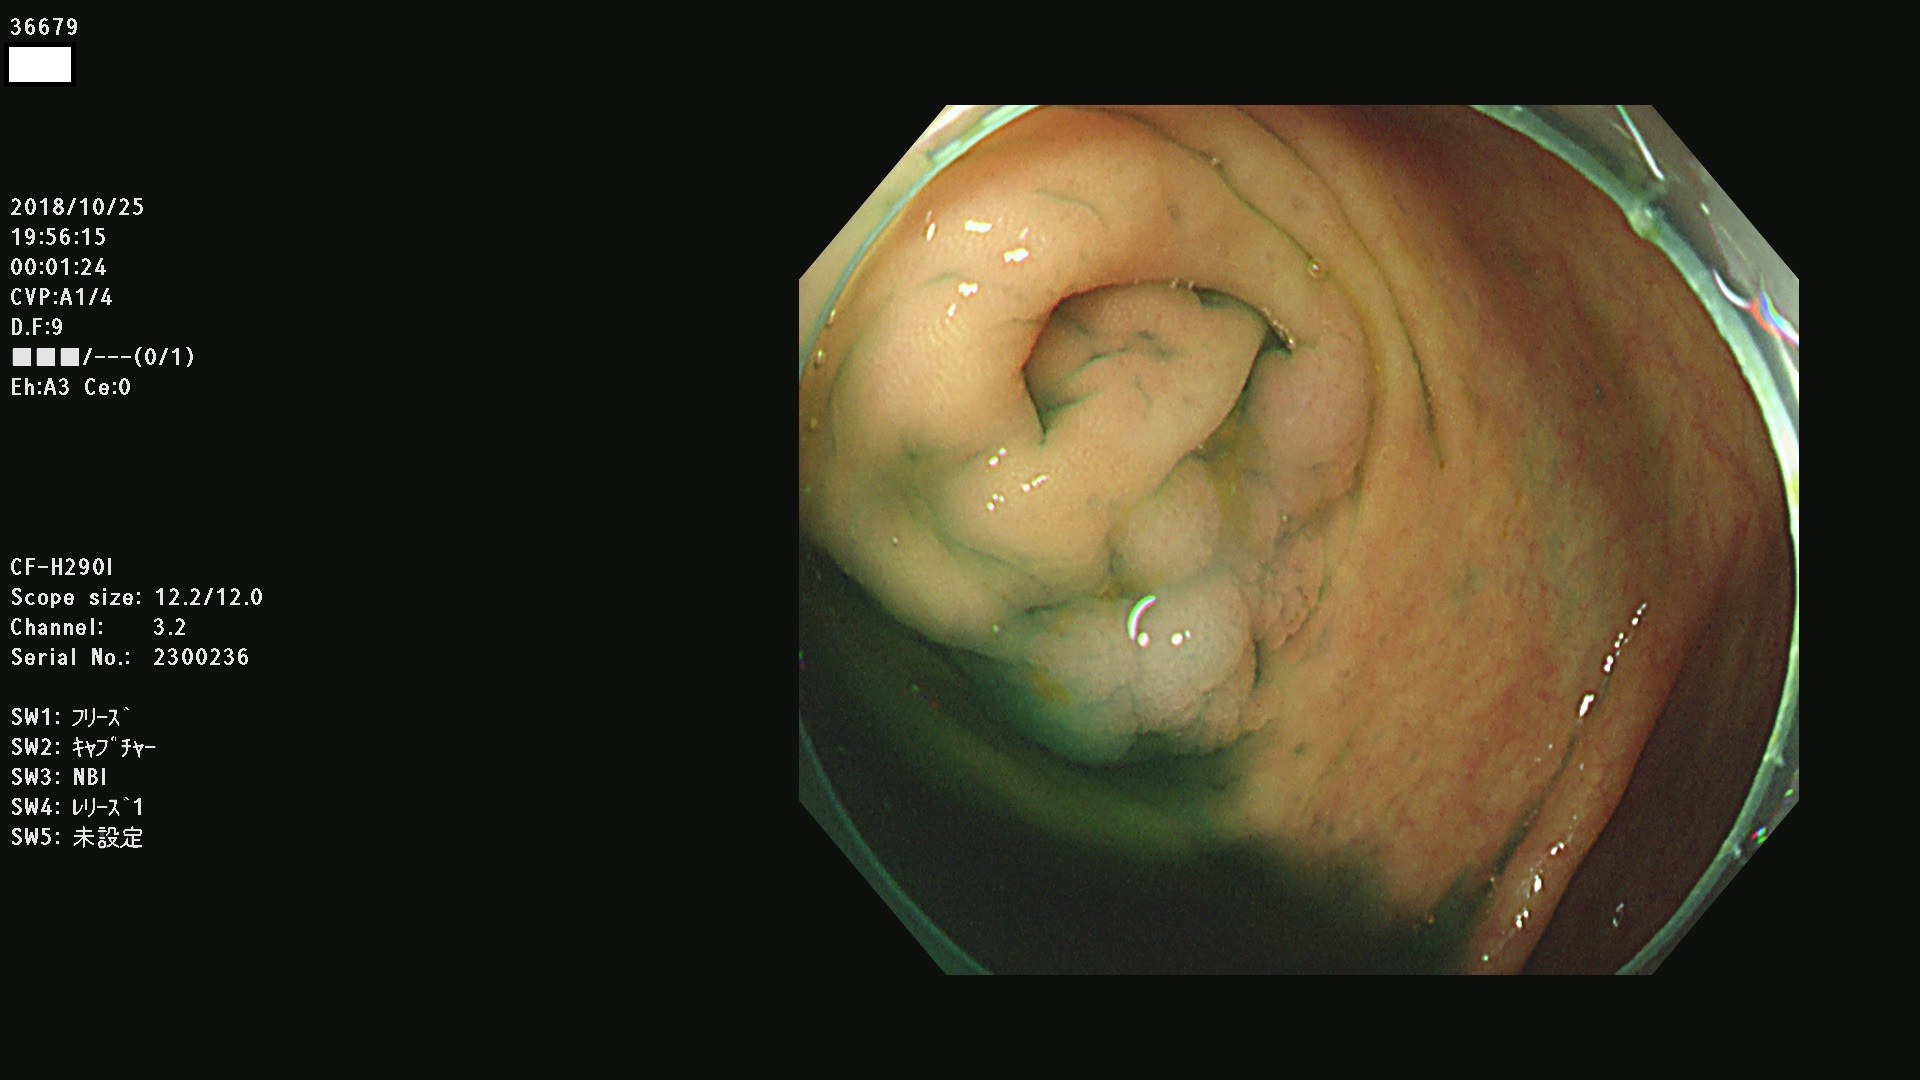

36600 36601 36603 36605 36606 36608 36609 36610 36611 36612 36613 36615 36617 36620 36621 36624 36625 36626 36627 36628 36629 36631(SSAPのみ) 36632 36633 36634 36636(SSAPのみ) 36637(SSAPのみ) 36639 36640 36642 36643 36644 36646 36647 36648 36649(SSAPのみ) 36650(SSAPのみ) 36652 36653 36654 36655(SSAPのみ) 36656 36657 36658 36659 36660 36661(SSAPのみ) 36665 36668 36669 36672 36673 36676 36677 36678 36679 36681 36682 36683 36684 36685 36687(SSAPのみ) 36691 36692 36693 36694 36695 36696 36697 36699(SSAPのみ)